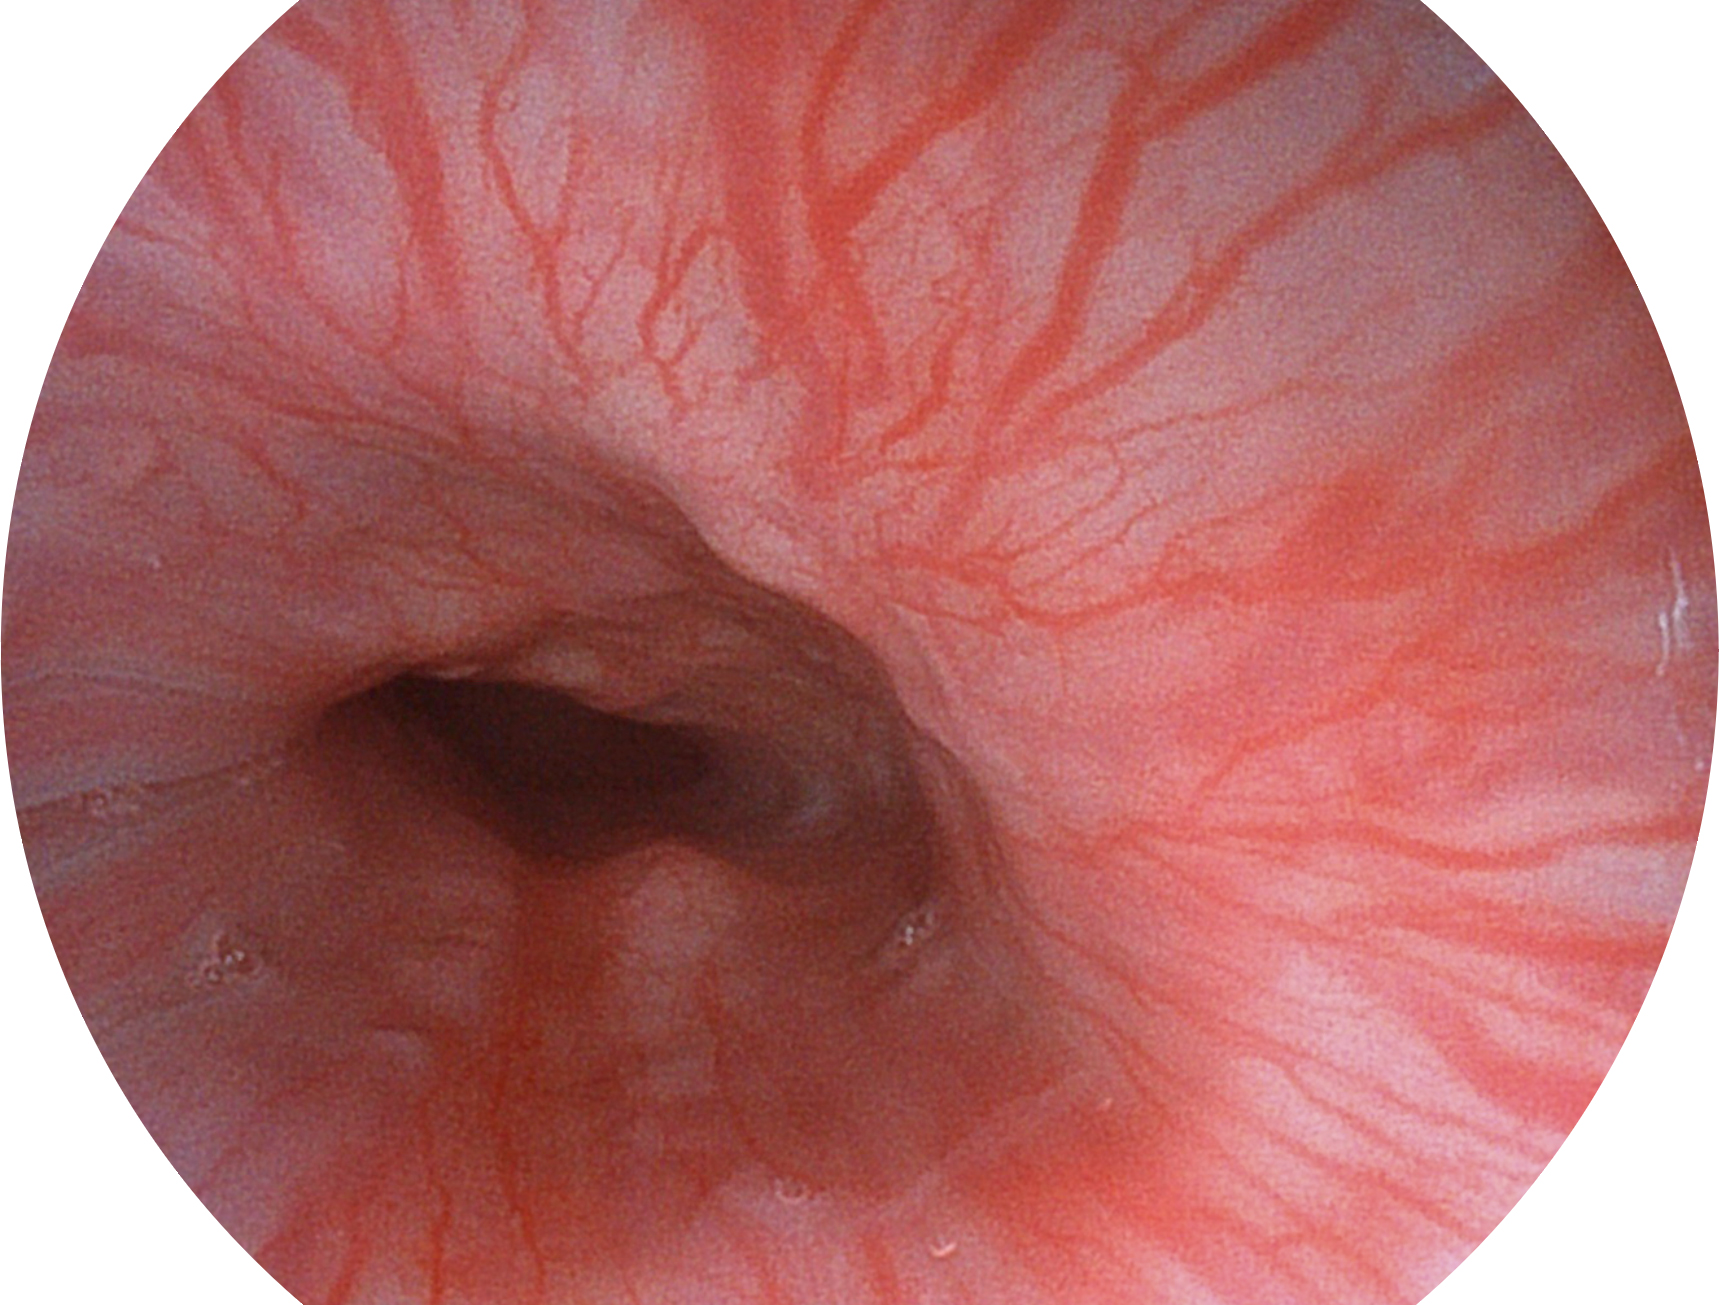

• 白光图像 VIST图像